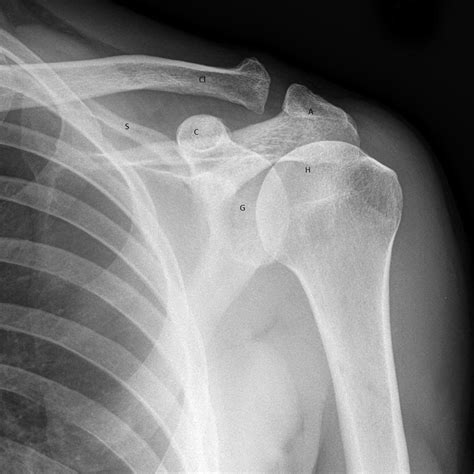

An Ac Joint X Ray is a diagnostic imaging technique used to visualize the acromioclavicular joint. This type of X-ray provides detailed images of the bones and the surrounding structures, helping healthcare professionals to diagnose injuries, fractures, or other abnormalities in the AC joint. The procedure is non-invasive and relatively quick, making it a preferred method for initial assessments of shoulder pain.

Interpreting the results of an Ac Joint X Ray requires a trained eye. Radiologists look for specific signs and abnormalities that indicate various conditions. Here are some key points they consider:

• Joint Space: The space between the clavicle and scapula should be uniform. Any narrowing or widening can indicate injury or degeneration.

• Bone Alignment: The bones should be properly aligned. Any displacement or misalignment can suggest a fracture or dislocation.

• Bone Density: Changes in bone density can indicate conditions like osteoporosis or bone tumors.

• Soft Tissue: While X-rays primarily show bones, they can also reveal some soft tissue abnormalities, such as swelling or calcification.